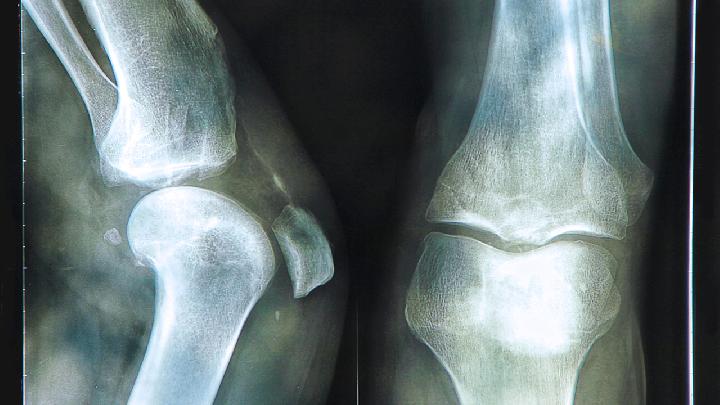

肋软骨炎指的是胸肋软骨与肋骨交界处非炎症性的肿胀疼痛。其原因一般被认为与劳损或者外伤有关,好发于上臂部长期持重的劳动者门。主要通过中医以及西药治疗。中医采取保守的治疗方法,例如可使用中药肋软骨炎散进行治疗。了解肋软骨炎临床表现,可以使我们在生活中提高乐对肋软骨炎的警惕性,从而使我们降低了肋软骨炎给我们带来的困扰。 2、肋软骨炎做什么检查呢,B超可以显示肋软骨肿胀以及结构改建,容易与双侧对比观察肿胀变化。 3、肋软骨炎做什么检查呢?CT能够很好地显示软骨肿胀及骨化的症状。 4、肋软骨炎做什么检查之MRI能够显示骨、软骨、滑膜及骨髓的活动性炎性改变,特异性和敏感性较高。 5、肋软骨炎做什么检查之实验室检查、血常规、血磷、血钙、血沉、碱性磷酸酶等均可正常。 以上就是针对于肋软骨炎做什么检查的问题的简单介绍,供大家参考。 关于软骨的信息![]() 肋软骨炎开刀大概多少费用?这是每个肋软骨炎患者都关心,也是最不放心的事情,因为现在很多的医院出现不明的收费情况,导致钱都不知道花到哪里了,今天我来给大家介绍一下,肋软骨炎开刀大概多少费用? ![]() 多年的肋软骨炎怎样运动?肋软骨炎虽然不是什么大疾病,但是如果长期久拖不治也是会造成巨大危害的,该疾病有一定的复发率,有的患者甚至多年患病,仍旧迁徙不愈,那么,对于多年的肋软骨炎怎样运动比较科学呢?下面为大家做详细介绍。 ![]() 肋软骨炎的出现,会引起患者局部疼痛剧烈,严重影响患者生活和工作,并造成一定的精神负担,2-5肋软骨处压痛若不及时彻底治疗,有反复发作趋势,对于肋软骨炎需警惕五大危害,下面为大家做详细的介绍。 ![]() 女性肋软骨炎应该怎么护理?女性是肋软骨炎的高发人群,虽然生活中很多人对该疾病不是很了解,有的甚至没有听说过,但是它的发病率在临床却是很高的,那么,对于女性肋软骨炎应该怎么护理比较好呢?一起来了解一下吧。 ![]() 说起肋软骨炎很多女性朋友都不是很了解,但患有这个病的人群中女性占的比例却是非常大的,那么,这个病是跟女性的生理特点有关系呢,还是日常的工作生活压力大引起的呢,下面让我们一起看看肋软骨炎形成的原因。 ![]() 肋软骨炎高发原因有哪些?肋软骨炎的发生,严重影响了患者的生活和工作,并且在夜间寒冷时疼痛会加剧,有时平卧疼痛也会加剧,导致夜不能眠,以致白天精神萎靡,无法专心工作,那么,肋软骨炎高发原因有哪些呢? ![]() 感染性肋软骨炎需要预防方法是什么呢?肋软骨炎在生活中比较常见,相信大家多少还是有一些了解的,但是提到对于肋软骨炎的具体预防方式,可能大家就不太清楚了,那么到底感染性肋软骨炎需要预防的方法是什么呢?一起来了解一下吧。 ![]() 对外科疾病有一些了解的人可能知道,肋软骨炎是外科中较为常见的疾病,这个病常见于女性患者,可以说对女性的身体健康造成了很严重的威胁,那么肋软骨炎表现类型都有哪些呢,下面让我们一起了解一下。 ![]() 肋软骨炎的护理原则是什么?肋软骨炎这种疾病在临床的发病率并不低,该疾病属于临床外科的一种高发病,且高发人群为20~30岁的女性,很多人在平时不注重疾病的护理原则,结果导致肋软骨炎延袭不愈,不见好转,那么,肋软骨炎的护理原则是什么呢? ![]() 肋软骨炎大概需要花费多少钱?在治疗疾病的时候,尽管到处排队很多时候忙的不知道花了多少钱,但是我们还是会计算一下大概的费用,下面我们一起了解下,肋软骨炎大概需要花费多少钱吧! ![]() 不管是什么样的疾病都是有引起这个病的原因存在的,不然也就不存在疾病了,肋软骨炎的疾病是很常见的,病情是很严重的,所以患者是一定要注意身体的变化情况的,要及时的调整好心情,找出发病的原因对症治疗的,下面讲讲肋软骨炎患者的饮食注意事项。 |